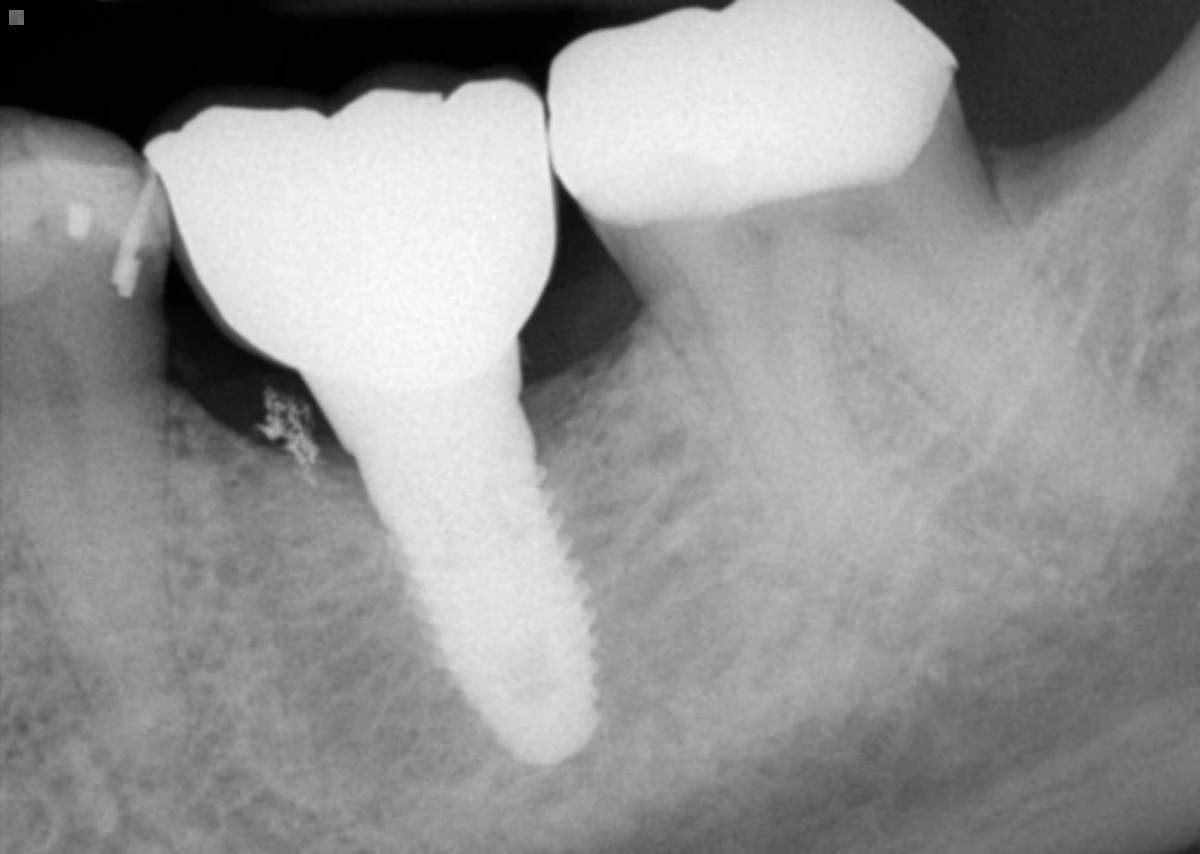

Residual cement is a frustrating problem in implant dentistry. When screw-retention is not possible, cement retained crowns are an excellent choice as they offer simplicity and a cost effective solution. In the previous newsletters we showed you techniques of using copy abutment and retrieval matrix to mitigate these problems. In this newsletter, we share a very simple and powerful clinical pearl to reduce the risk of failure to detect residual cement.

Clinical studies have shown that immediate post-operative peri-apical or vertical bitewing radiographs are effective in ruling out residual cement in at least 50% of the crown surfaces (mesial and distal). Of course any excess cement at buccal and lingual surfaces can only be detected clinically and best to prevent them from happening. Taking an immediate post-operative radiograph can also aid in defending against accusation of any negligence and aid in medical-legal record keeping.

A second important and simple pearl is to schedule patients for a 2 or 3-week quick follow-up to examine soft tissue response clinically and to detect any clinical signs of residual cement (hopefully none!) Clinical studies have shown that most residual cement issues are identified within 3 weeks. It would make sense for you the treating clinician to detect this issue rather than the patient disappearing away on you or another dentist taking an x-ray and detecting any residual cement. Below is an example of a patient who presented to us with symptoms after having an implant crown cemented recently at another office.